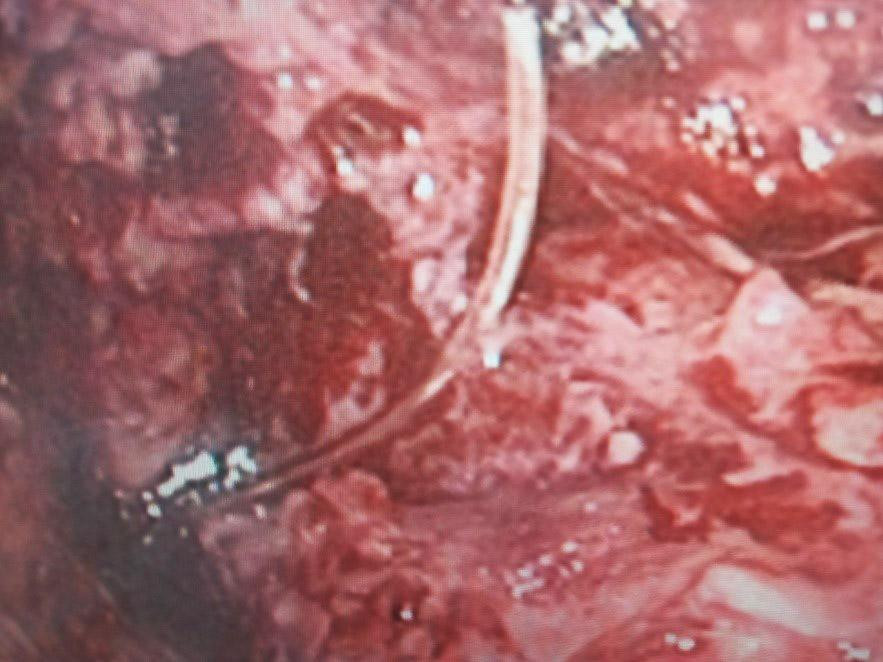

| Chiếc xương cá xuyên thủng đại tràng được phát hiện trên hình ảnh camera phẫu thuật nội soi |

Bằng phương pháp phẫu thuật nội soi ê kíp bác sĩ khoa Ngoại Tổng hợp đã gỡ các tổ chức bao quanh khối viêm ở ruột, phát hiện chiếc xương cá xuyên thủng từ trong đại tràng ngang ra ngoài với kích thước 30mm x 1,5mm. Vị trí thủng đã rò rỉ chất thải vào ổ bụng gây nhiễm trùng nặng.